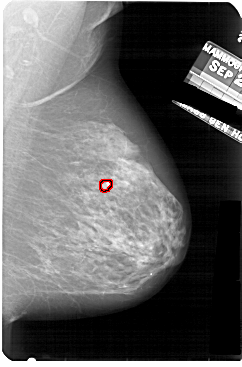

A_1859_1.LEFT_MLO

LEFT_MLO LINES 5191 PIXELS_PER_LINE 3736 BITS_PER_PIXEL 12 RESOLUTION 43.5 NON_OVERLAY